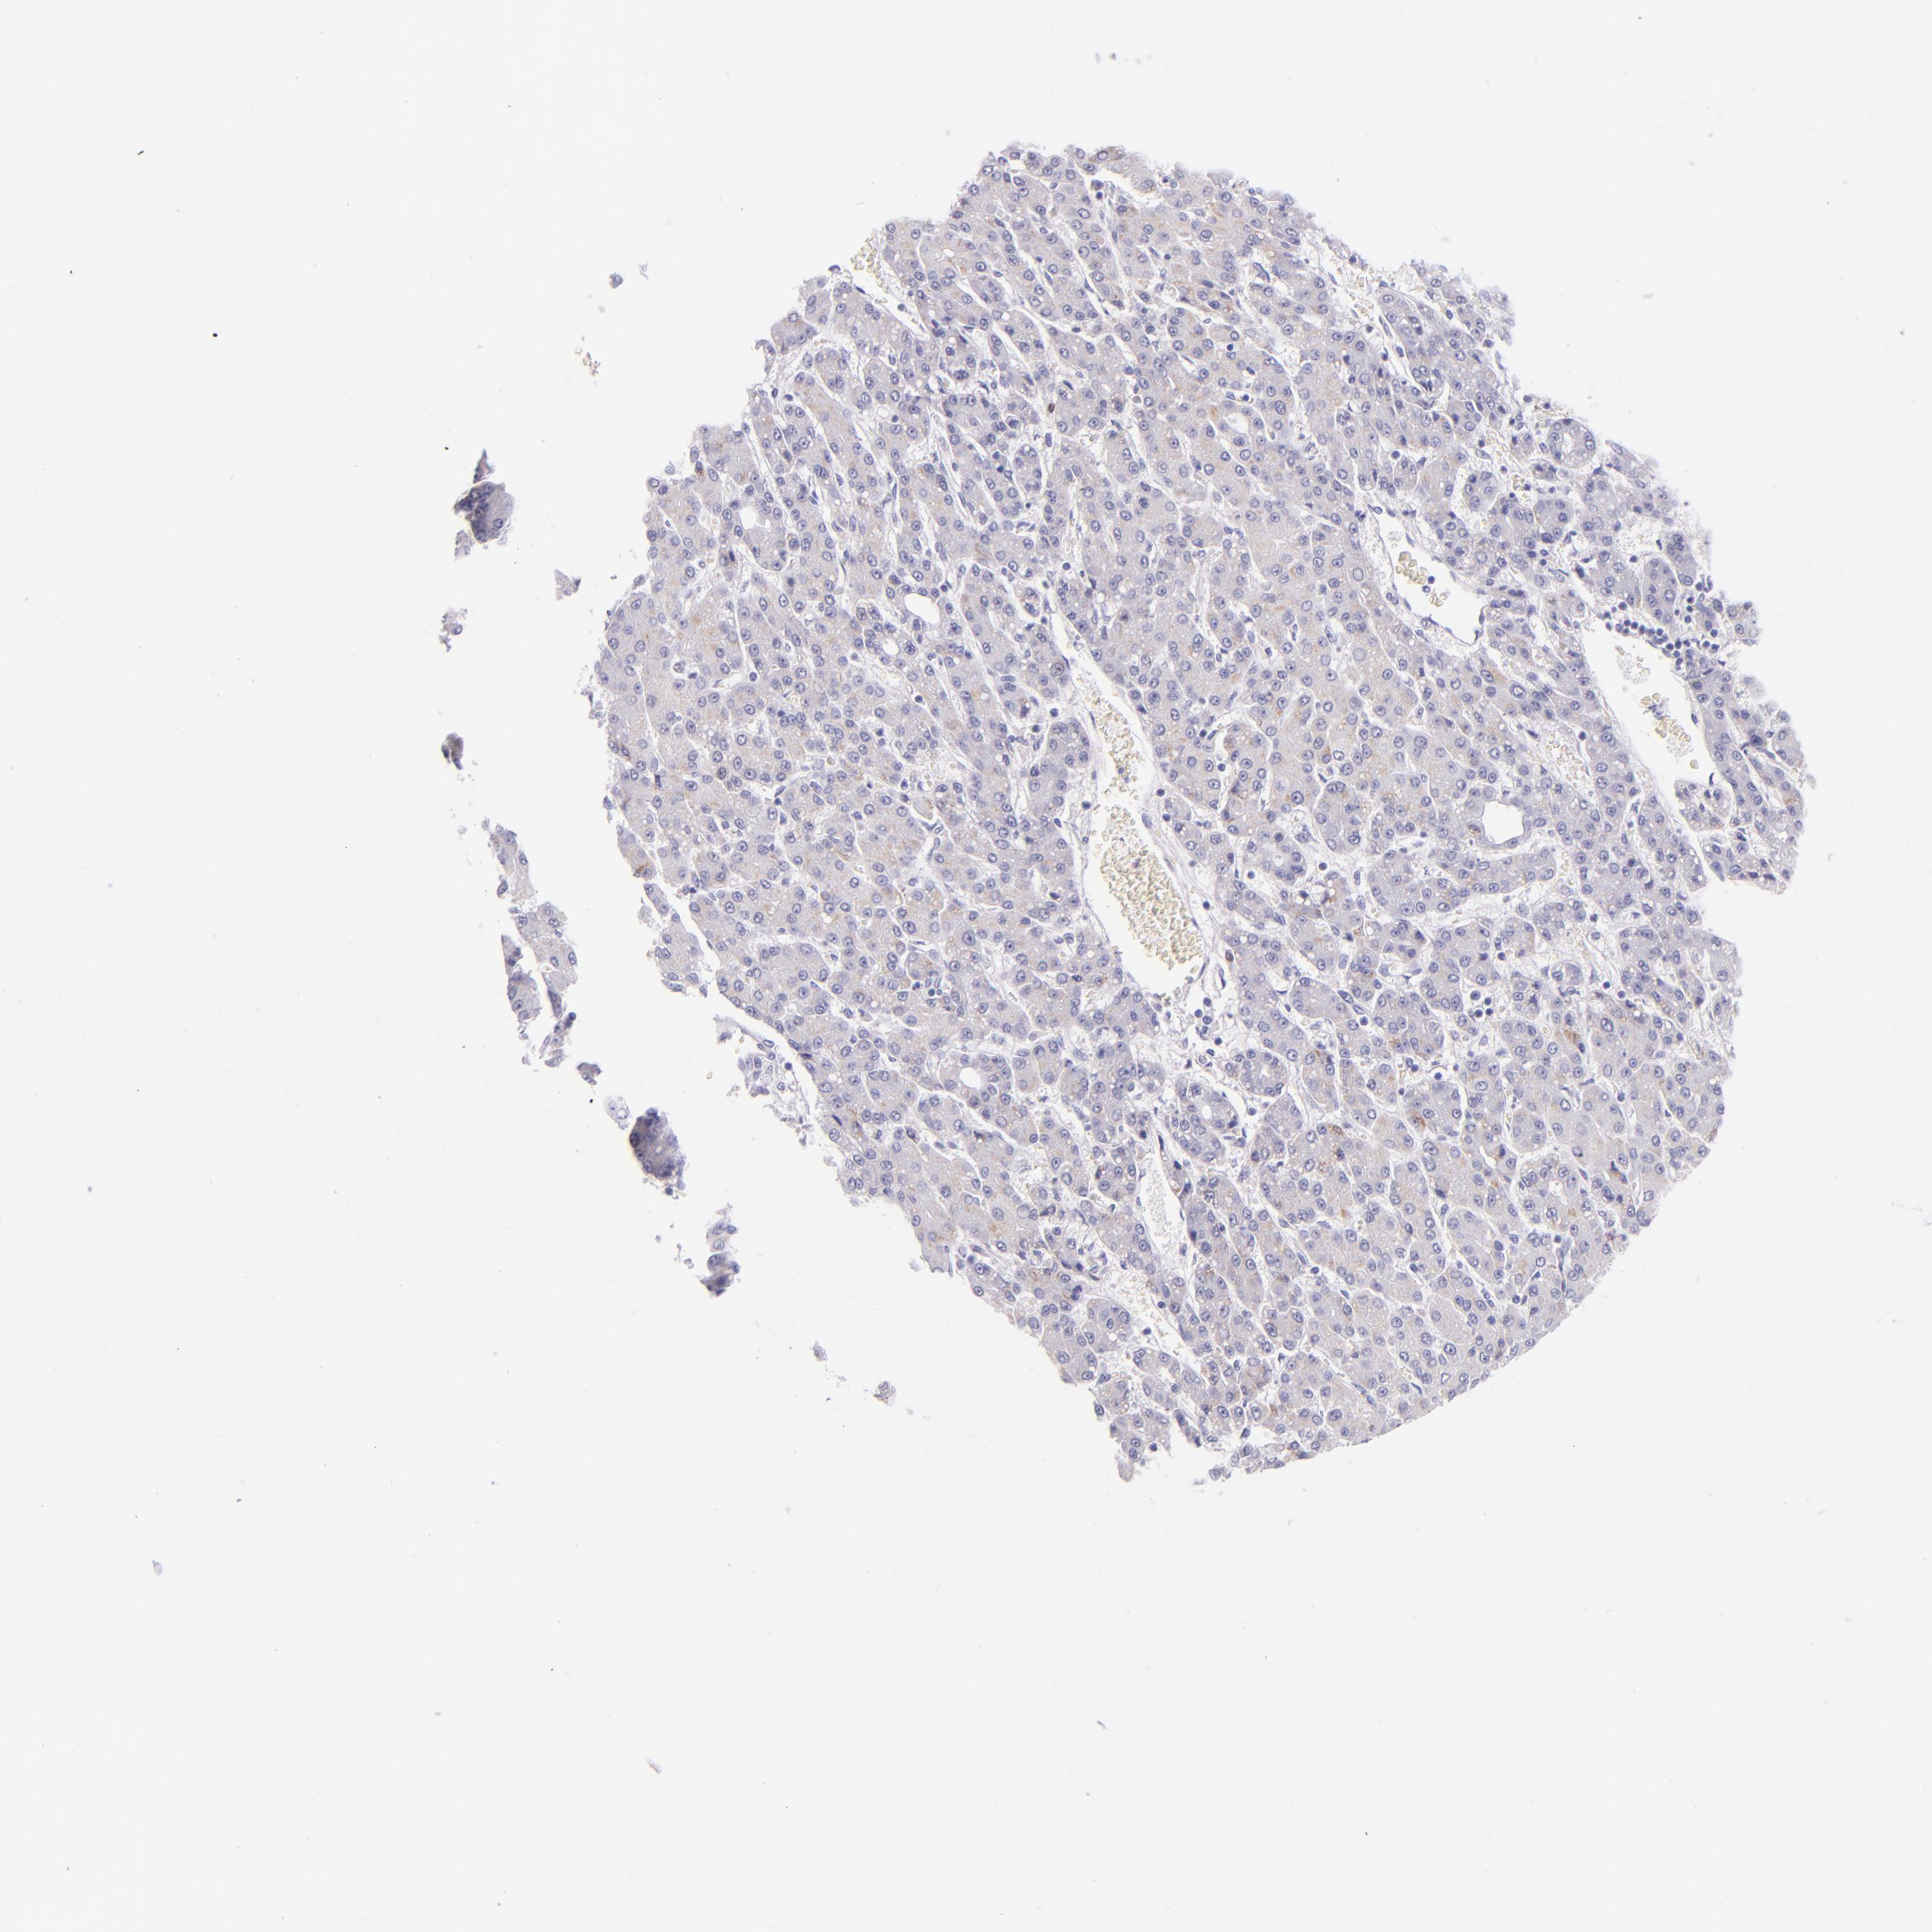

LIVER CANCER - Protein expressioni

A mouse-over function shows sample information and annotation data. Click on an image to view it in a full screen mode. Samples can be filtered based on level of antibody staining by selecting one or several of the following categories: high, medium, low and not detected. The assay and annotation is described here.

Note that samples used for immunohistochemistry by the Human Protein Atlas do not correspond to samples in the TCGA dataset.

Antibody stainingi

Antibody staining in the annotated cell types in the current human tissue is reported as not detected, low, medium, or high, based on conventional immunohistochemistry profiling in selected tissues. This score is based on the combination of the staining intensity and fraction of stained cells.

Each image is clickable and will lead to virtual microscopy that enables deeper exploration of all samples and also displays staining intensity scores, fraction scores and subcellular localization as well as patient and tissue information for each sample.

Antibody HPA002038

Antibody HPA002698

Antibody CAB013508

Cholangiocarcinoma

Carcinoma, Hepatocellular, NOS